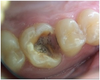

Après la dépose de l'amalgame, on aperçoit le trait de fracture.

Cette paroi de la dent est mobile.